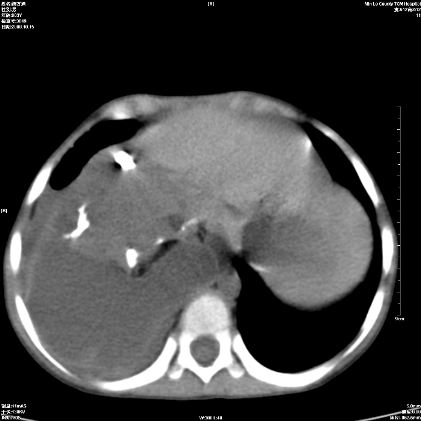

标题: PED1609:男性,3岁。彩超示肝Ca. [打印本页]

标题: PED1609:男性,3岁。彩超示肝Ca.

考虑后纵隔恶性畸胎瘤伴肝内多发转移可能性大,右侧肾上腺转移不除外.

3岁;肝低密度灶;有钙化;有转移灶;考虑肝母细胞瘤;查afp

支持肝母细胞瘤肝内转移

考虑神经母细胞瘤并肝转移